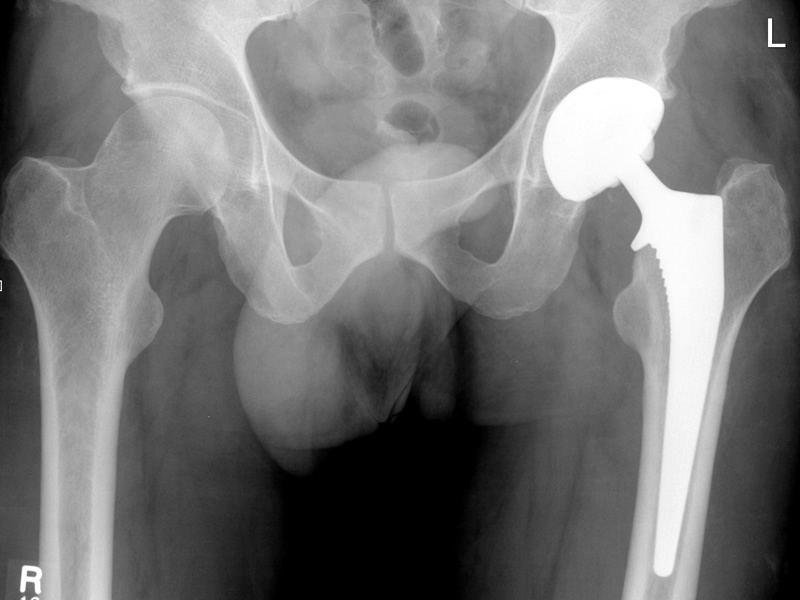

Do I need a new hip

Do I need a hip replacement

A lot of our patients, especially those over 50 ask us about hip pain. Typically, they are worried if they are going to need a hip replacement. The oxford hip socre is an easy test, that gives a good idea of whether a hip is likely to need replacing.

A score this low may indicate severe hip arthritis. It is highly likely that you may well require some form of surgical intervention, contact your GP for a consult with an Orthopaedic Surgeon. Chiropractic care is essential when the hip is severely degenerate to maintain as much movement and activity as possible before a hip replacement is performed.

A score of 20 to 29 may indicate moderate to severe hip arthritis. See your Chiropractor for an assessment and x-ray. Your Chiropractor may consider a referral to an Orthopaedic Surgeon. Chiropractic care will help relieve the pain from the hip until surgery can be performed.